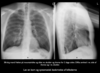

Normal rtg. af thorax:

- PA:

A

- Lateral: